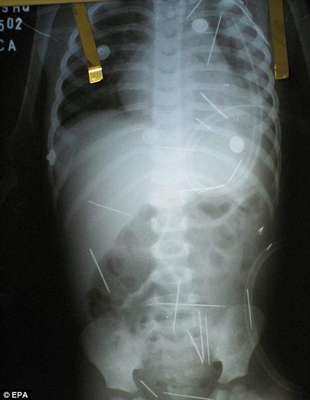

Un extraño caso médico se produjo en Brasil al descubrirse que un niño de dos años que se quejaba de dolores tenía 50 agujas clavadas en su cuerpo, sin presentar ninguna señal externa. La policía no tardó en descubrir que el culpable era el padrastro del niño, quien le insertó las agujas durante una serie de rituales de magia negra que duraron un mes y que fueron inspirados durante un sueño. La extracción de las agujas se prevé extremadamente complicada; algunas de ellas le atraviesan un pulmón, y otras tendrán que permanecer en su interior porque extraerlas sería más peligroso que dejarlas.